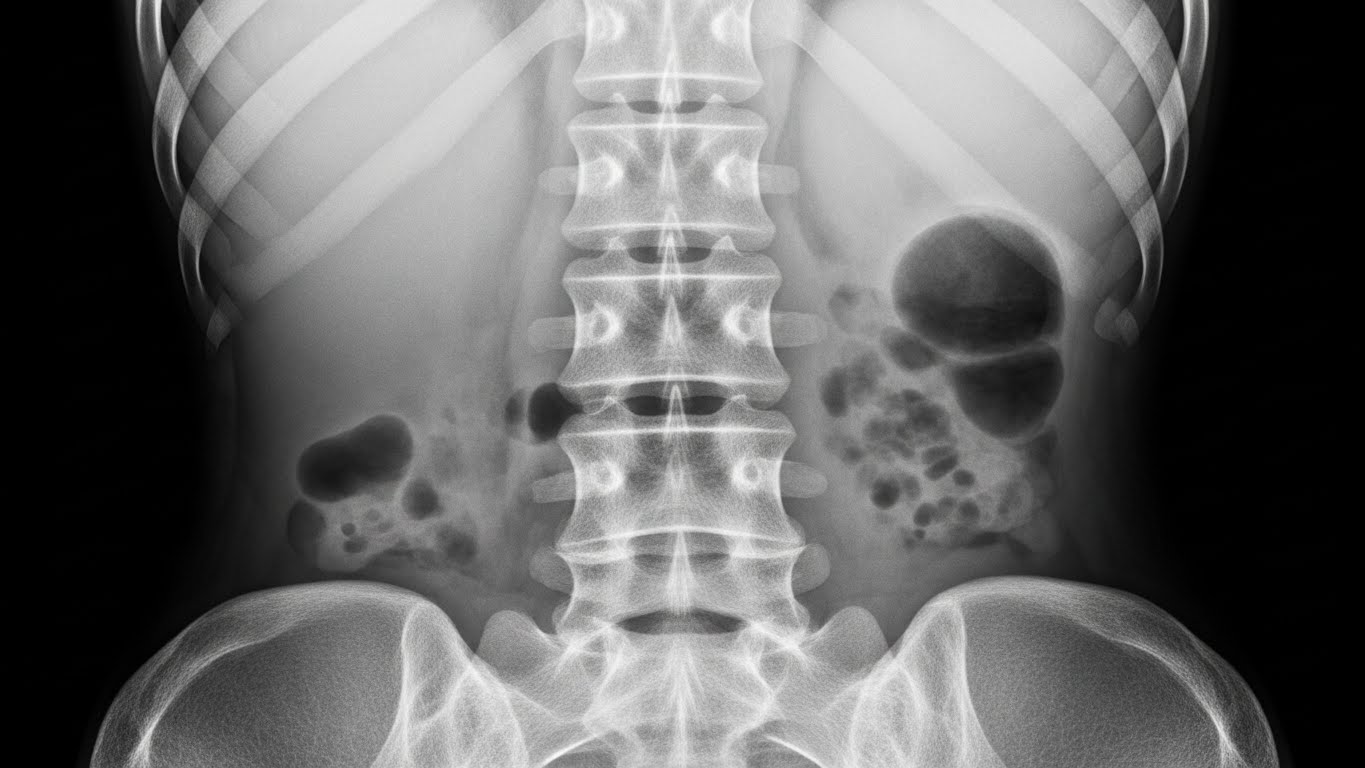

AI 기반 성장판 검사

척추 정렬 불균형

척추 정렬 불균형는 이 증상을 유발하는 주요 원인 중 하나입니다. 정확한 진단을 통해 원인을 파악하고 적절한 치료를 받는 것이 중요합니다.